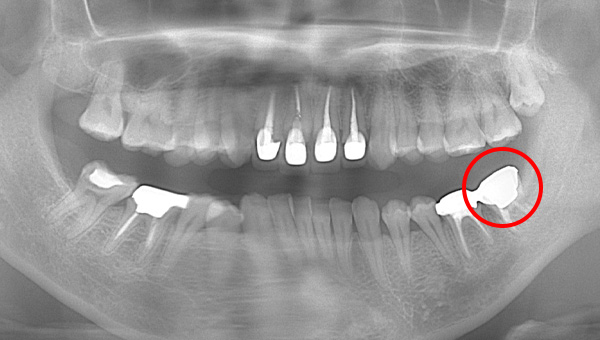

初診時のパノラマ

説明:

初診時のパノラマです。左下の一番奥の歯が虫歯になっているのがわかります。

初診時のパノラマレントゲン

初診時のパノラマレントゲンです。右上の歯が虫歯によって大きく欠けているのがわかります。